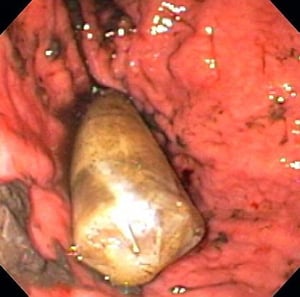

Gambar ini menunjukkan kemasan obat di dalam lambung.

Gambar disediakan oleh Alan Gingold, DO.